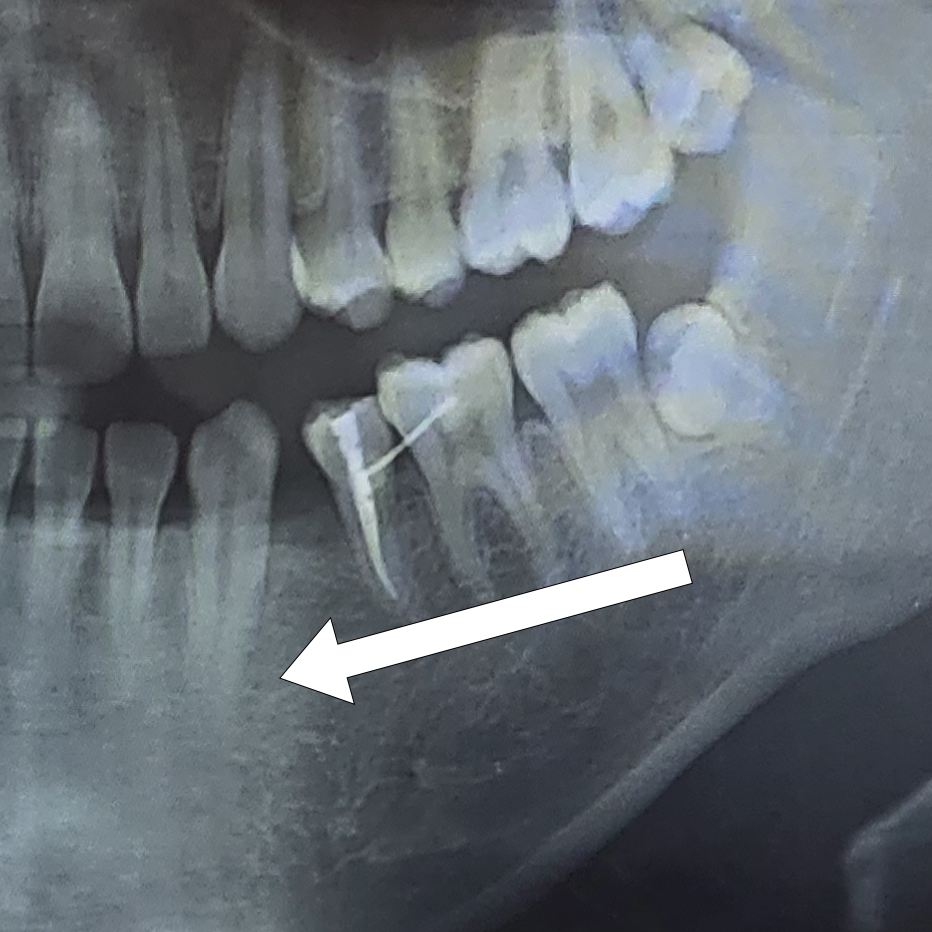

어금니를 교정으로 끌어오려면 어금니의 뿌리가 깊게 자리 잡은 데다가 어금니를 치아가 빠진 공간으로 하나씩 움직이느라 이동하는 데 시간이 오래 걸리고 아플 수 있다고 하셨다. 또 아랫니를 이동시키는 과정에서 뾰족한 아랫니가 윗니와 부딪힐 것이기 때문에 하악의 어금니를 깎아낼 필요가 있다고 한다.

원래 윗니와 아랫니는 지그재그 형태로 맞물려 있는데 내 경우에는 어금니를 이동시키다보면 이 지그재그 형태가 맞지 않을 가능성이 높다고 하셨다. 거기다 결손된 영구치 옆의 이(하악 좌측 제2소구치)는 신경치료를 한 상태인데 신경치료를 한 경우 교정이 불가능한 경우도 있다고 한다. 다행히 나는 가능할 것이라고 했다. 이런 이유들 탓에 교과서적으로 이상적인 치료 방법은 아니지만 영구치 결손을 치료하기 위해 시행할 것이라고 말씀해주셨다.

교정치료 초기에는 어금니를 하나씩 이동할 때 앞니를 지지대 삼아 당겨보고, 만약 앞니도 버티지 못하면 잇몸에 스크류를 박아 이동시킬 것이라고 한다. 사랑니 이동과 관련해서는 우선 경과를 보고 추후에 결정하시겠다고 했다. 교정 기간은 1년 반이나 그 이상이 걸릴 것이라고 한다.

부가적으로 현재 버티고 있는 오른쪽 아래턱의 유치에 대해서도 말씀해주셨다. 만약 하악 어금니가 빠져버린다면 교정은 못하니 그때는 임플란트를 하라고 하셨다. 파노라마 엑스레이 상으로 보이는 우측의 어금니는 크기가 크기 때문에 교정으로 당기기에는 무리가 있다고 한다.